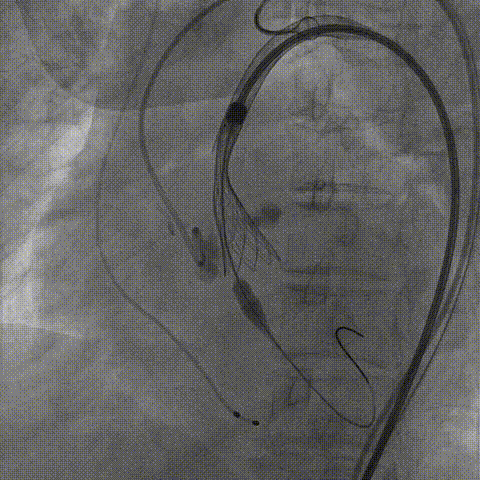

TaurusNXT植入过程

手术使用Z-Med 20mm球囊预扩两次,植入AV23 TaurusNXT主动脉瓣,Snare圈套器协助输送系统过弓、过瓣,120次/分起搏频率下,在左右重合位影像下释放瓣膜达到工作位,造影显示位置偏深,完全回收两次后释放达工作位,造影显示位置仍然不理想,之后第三次使用部分回收,精准释放瓣膜,之后使用Z-Med 20mm球囊后扩张两次。术后即刻超声心动图评估显示瓣膜位置良好,微量瓣周漏,主动脉瓣口峰值流速为1.90m/s,平均跨瓣压差为8mmHg,有效瓣口面积 1.60cm²,血流动力学指标理想。

Snare协助输送器跨瓣

瓣膜第一次释放至工作位造影

完全回收后瓣膜第二次释放

完全回收后瓣膜第三次释放

部分回收后瓣膜定位释放

球囊后扩张

瓣膜最终造影